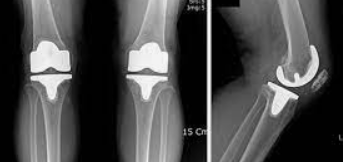

인공 관절 수술은 관절의 퇴행성 변화, 외상, 또는 다른 질환으로 인해 손상된 관절을 인공적인 재료로 만든 관절로 교체하는 의료 절차입니다. 이 수술은 주로 무릎, 고관절, 어깨 관절 등에 적용되며, 환자의 삶의 질을 향상시키고 통증을 감소시키는 데 목적이 있습니다.

인공 관절 수술의 종류는 크게 두 가지로 나뉩니다: 전치환술과 부분치환술입니다. 전치환술은 손상된 관절 전체를 인공 관절로 교체하는 방법이며, 부분치환술은 손상된 관절의 일부만을 교체하는 방법입니다. 환자의 상태와 필요에 따라 적절한 수술 방법이 선택됩니다.

전치환술은 관절의 변형이 심하거나 손상 부위가 넓은 경우에 주로 사용됩니다. 이 수술은 관절의 안쪽과 바깥쪽 모두를 인공 관절로 바꿔줌으로써, 통증을 줄이고 관절의 기능을 회복시키는 데 도움을 줍니다.